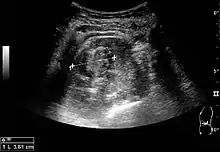

Renal ultrasonography

On renal ultrasonography, a solid renal mass appears in the US exam with internal echoes, without the well-defined, smooth walls seen in cysts, often with Doppler signal, and is frequently malignant or has a high malignant potential. The most common malignant renal parenchymal tumor is renal cell carcinoma (RCC), which accounts for 86% of the malignancies in the kidney. RCCs are typically isoechoic and peripherally located in the parenchyma, but can be both hypo- and hyper-echoic and are found centrally in medulla or sinus. The lesions can be multifocal and have cystic elements due to necrosis, calcifications and be multifocal (Figure 8 and Figure 9). RCC is associated with von Hippel–Lindau disease, and with tuberous sclerosis, and US has been recommended as a tool for assessment and follow-up of renal masses in these patients.[3]